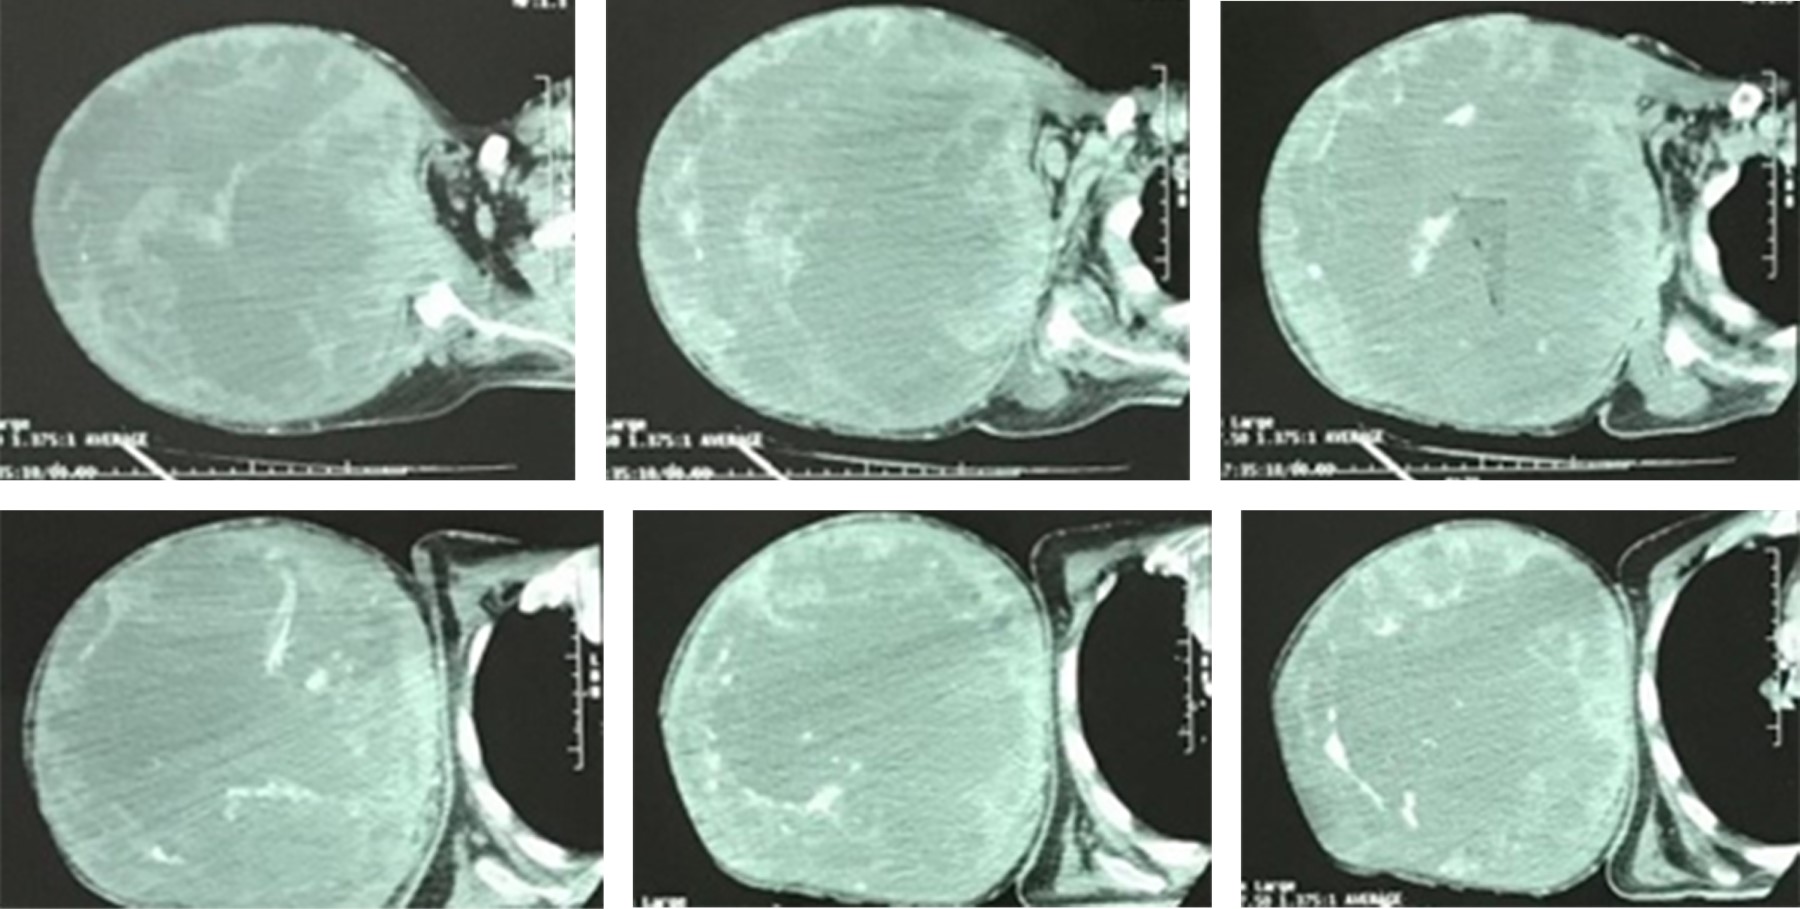

A la exploración física, consciente, orientado, cooperador, con palidez de piel y tegumentos +++. Cuello cilíndrico, móvil, tráquea central, Mallampati modificado II. Bellhouse-Dore: grado 1. Con tumoración de miembro torácico derecho de aproximadamente 30 × 40 cm, a tensión y con trama vascular aumentada, edematizada y dolorosa a la palpación y a la movilización, pulsos radial y cubital ipsilateral disminuido en intensidad. Resto sin alteraciones. Talla: 1.60 m. Peso: 58 kg. Peso predicho: 56.9 kg. Se anexa tomografía axial computarizada (Figuras 1 y 2).

Posteriormente, da comienzo el evento quirúrgico. Como hallazgo quirúrgico se realizó disección por planos hasta llegar a hueco axilar, subiendo hasta clavícula se liga vena y arteria subclavia; se liga plexo nervioso, se disecan músculos de inserción humeral, se desarticula cabeza del húmero y se retira conjuntamente con omóplato ipsilateral, verificando homeostasia y cierre por planos (Figura 4).

Figura 2